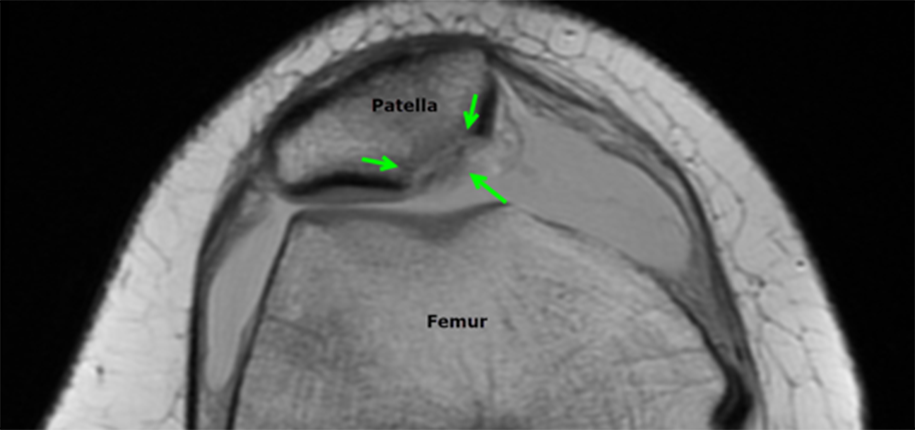

The diagnosis is typically made by history and physical examination. Knee x-rays are obtained initially to look for bone injuries, but cannot fully show the extent of soft tissue damage. For this reason, an MRI is performed soon after to assess the ligaments and cartilage and help determine whether surgery will be necessary. The MRI will also show underlying anatomical features that may predispose to the instability of the patella. If there is a significant injury to the cartilage covering the bone, a loose fragment in the joint, or tearing of the main ligament that stabilizes the patella, surgical treatment is recommended.

Luckily for Patrick Mahomes, the MRI did not show damage to the cartilage or ligaments. He was treated medically with physical therapy and able to return to play in a couple of weeks. The child with the MRI below was not as fortunate and required surgery to repair the patella. After a patellar dislocation, there is an increased risk of a recurrent dislocation, so continued follow-up and therapy are necessary.